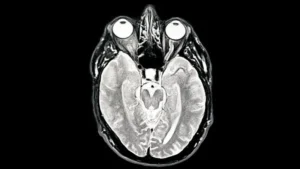

Los hallazgos forman parte de un estudio en el que participaron alrededor de 4.000 personas de hasta 90 años, quienes se sometieron a escáneres que mostraron las conexiones entre sus neuronas.

Estos patrones solo se han revelado ahora gracias a la cantidad de escáneres cerebrales disponibles en el estudio, publicado en la revista Nature Communications.